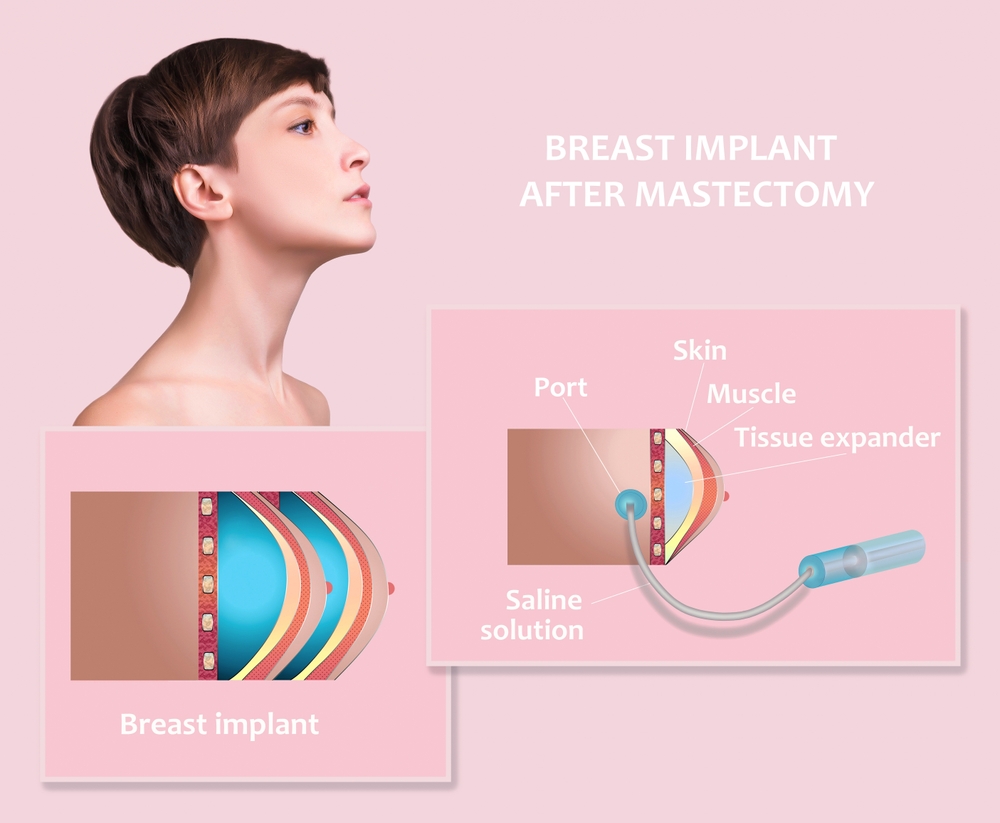

Skaityti daugiauDetailsKrūtų sandara: pieno latakai, audiniai, ligos ir fiziologija

Krūtys yra svarbi ir sudėtinga moters kūno dalis, tačiau jas turi ir vyrai. Nors moters krūtys yra svarbios tiek fiziologiškai...